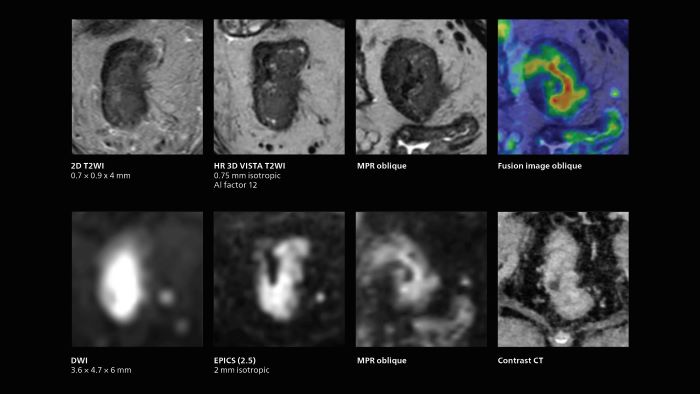

MRI of rectal cancer

In this patient MRI was done to help in diagnosing the depth of invasion. Performed on Elition X.

Notable improvement in diffusion-weighted imaging

With SmartSpeed, Kumamoto Chuo Hospital also has the ability to use EPI diffusion-weighted imaging (EPICS-DWI) with Compressed SENSE, which is an important step forward according to Dr. Katahira. “Before, our EPI diffusion was performed using SENSE, but now with Compressed SENSE it is possible to obtain very clear images,” he says. He also describes the benefit of being able to perform 3D diffusion-weighted imaging. “Previously, we only had DWI images in one direction to make a diagnosis. Now, we can do something that was not possible before: performing a DWI volume acquisition so that multiplanar reconstruction can be used, allowing us to look at scan results from all directions to make the diagnosis,” Dr. Katahira says. “What used to be a diagnosis based on just cross-sectional images, can now be based on a volume image. This is a dramatic improvement for us, because it is now possible to look at slices in various cross section directions. For example, the presence or absence of venous invasion is very important in rectal cancer patients, because venous invasion can cause metastasis in the future. The ability to reconstruct images according to the direction of the blood vessels, allows us to see venous infiltration more realistically, which is a world of difference from what we were used to.”